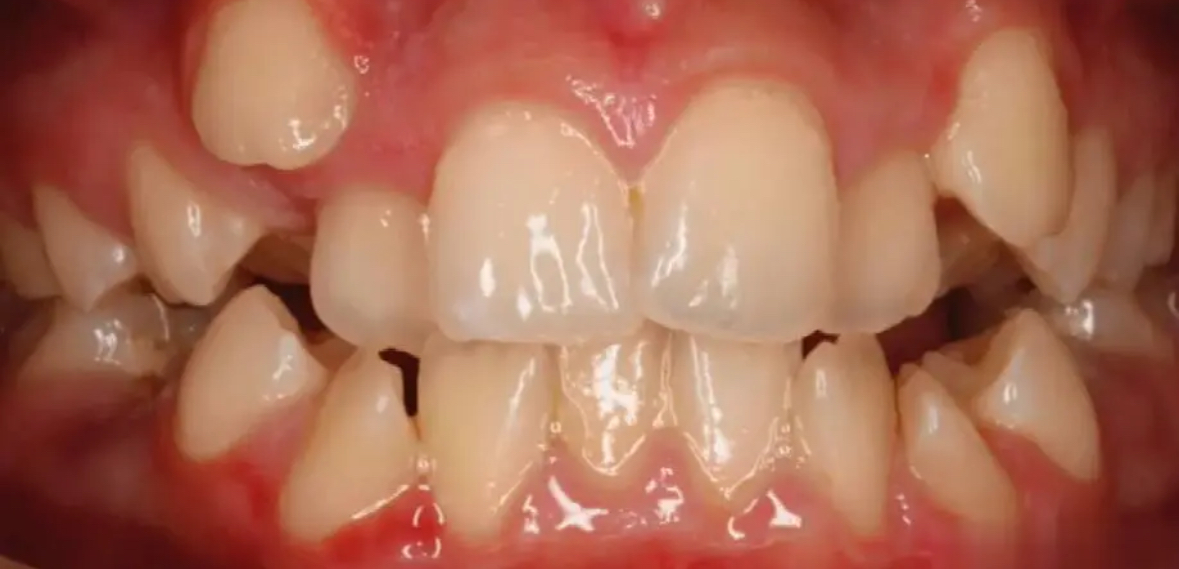

齙牙,也叫“前突牙”或“牙齒前突”,是常見的牙齒畸形之一,主要表現為上前牙或下前牙向前突出,影響面部美觀和咬合功能。很多家長在孩子換牙期發現牙齒不齊、嘴唇外突等問題時,常常會問:“現在帶孩子去矯正還來得及嗎?”、“成人還能矯正齙牙嗎?”

一、什么是齙牙?它有哪些類型?

首先,我們要明確一點:齙牙并不等于牙齒不整齊,它是一種特定類型的牙齒或骨骼異常:

牙性齙牙:主要是牙齒排列異常導致,上下前牙過度傾斜前突;

骨性齙牙:由頜骨發育異常引起,如上頜骨過長或下頜骨發育不足;

功能性齙牙:長期口呼吸、吮指等不良習慣也可能導致類似癥狀。

二、兒童時期:矯正齙牙的“黃金窗口期”

一般來說,7~12歲是兒童進行早期干預的黃金年齡段,尤其是對于牙性和部分功能性齙牙。